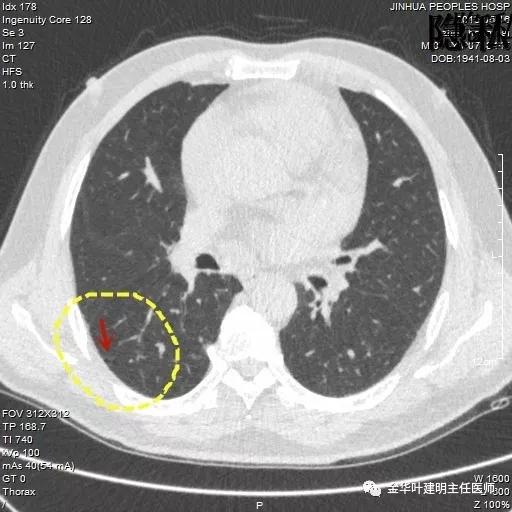

考虑恶性,那么就得考虑住院并行手术治疗,入院后再进一步查靶扫描,结果如下:

是不是囊腔型腺癌?周围病灶,有空腔,有磨玻璃成份,当然要考虑,但我觉得因为似乎是以往是空腔性病变,今年其内部分填充了实性成分,要考虑粘液腺癌可能为大。当然反正都得手术切除治疗。